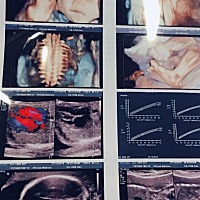

大家看看男宝女宝

大家看看像男宝 女宝